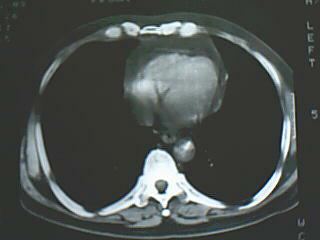

左侧中央型肺癌伴阻塞性肺炎

片子不太清,纵隔窗观察病灶内似可见散在斑点样钙化影,考虑结核可能性大。

片子不太清,纵隔窗观察病灶内似可见散在斑点样钙化影,结合病史考虑结核可能性大,但是最好做支气管镜排除肺癌。

纵隔淋巴结钙化明显,病史两年,首先考试tb.